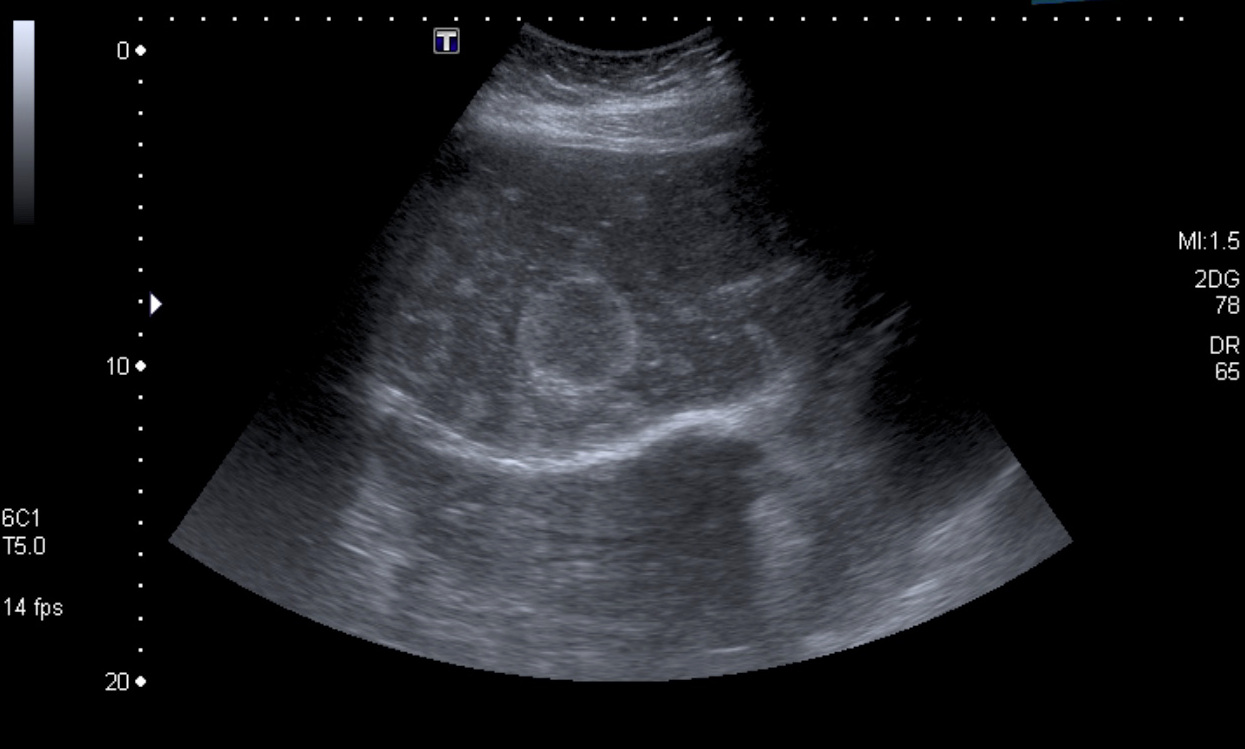

Paciente de 12 años con dolor abdominal. Remitida para estudio de masa intraabdominal.